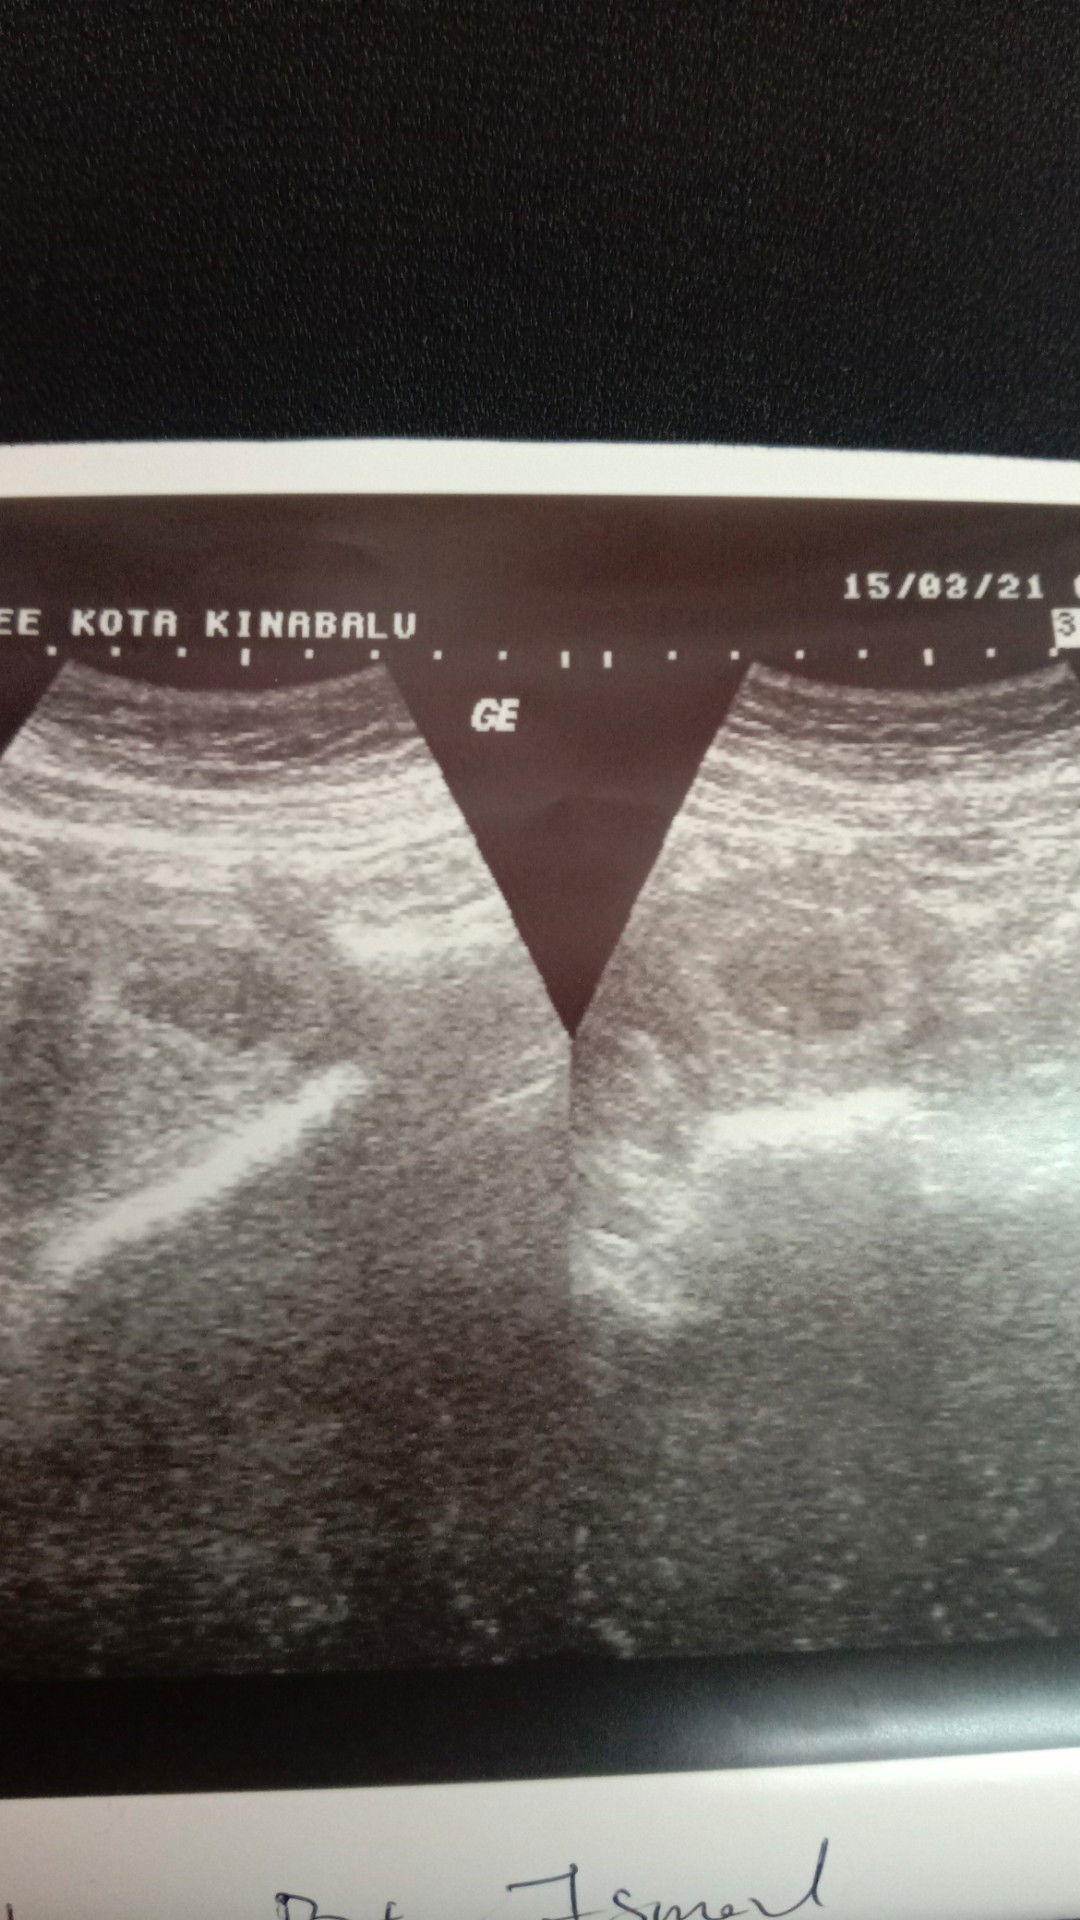

Hari ni dtg PAC sbab ada rsa air jernih kluar pkul 1 am tdii..lpas tu buat ctg kontraksi mmg kuat,.os pulak 1cm..doktor ckp kmungkinan pre term labour sbab air ketuban leaking dh...sya hari ni tepat2 36.mgu...sedih dan takut sbab baby pra matang klu lahir mgu ni😭😭😭doakn sya dprmudahkn ye#firstbaby #1stimemom #pregnancy